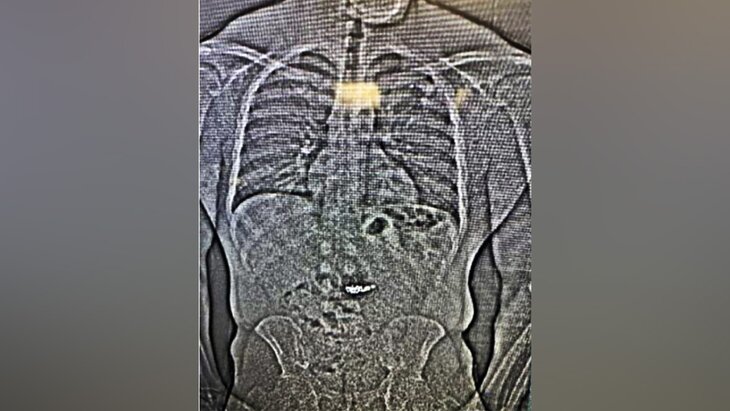

В американском штате Флорида подозреваемый в краже проглотил две пары бриллиантовых сережек Tiffany&Co., цена которых составляет около 770 тысяч долларов, во время задержания на обочине шоссе. Об этом сообщает RT со ссылкой на CNN.

По данным издания, мужчину доставили в медучреждение, где ему провели рентген. При этом на данный момент серьги все еще не извлекли.